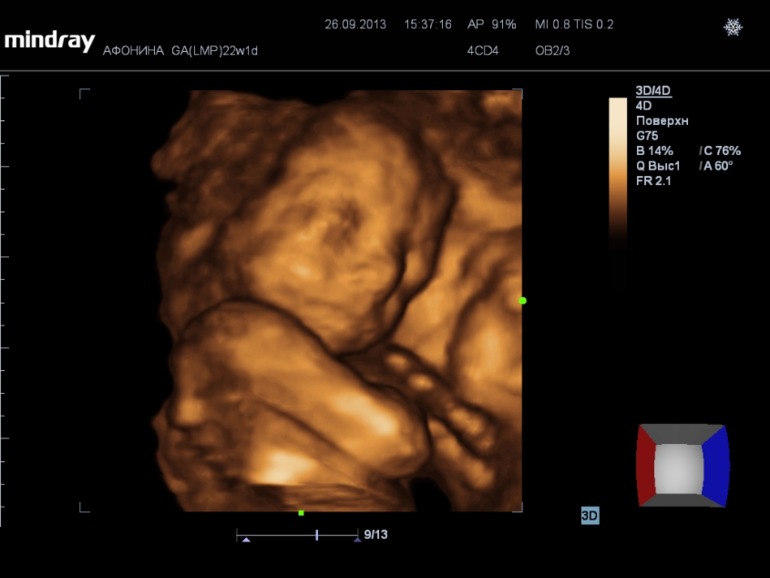

На 3d нам сказали что ребеночек ну очень щекастый, нос картошкой))) Наделали кучу фото и видео (запись на диск 300р), насмотрелись вдоволь. А в самом конце нам сказали пол.....

А вот и фото нашей принцессы))) (под кат)